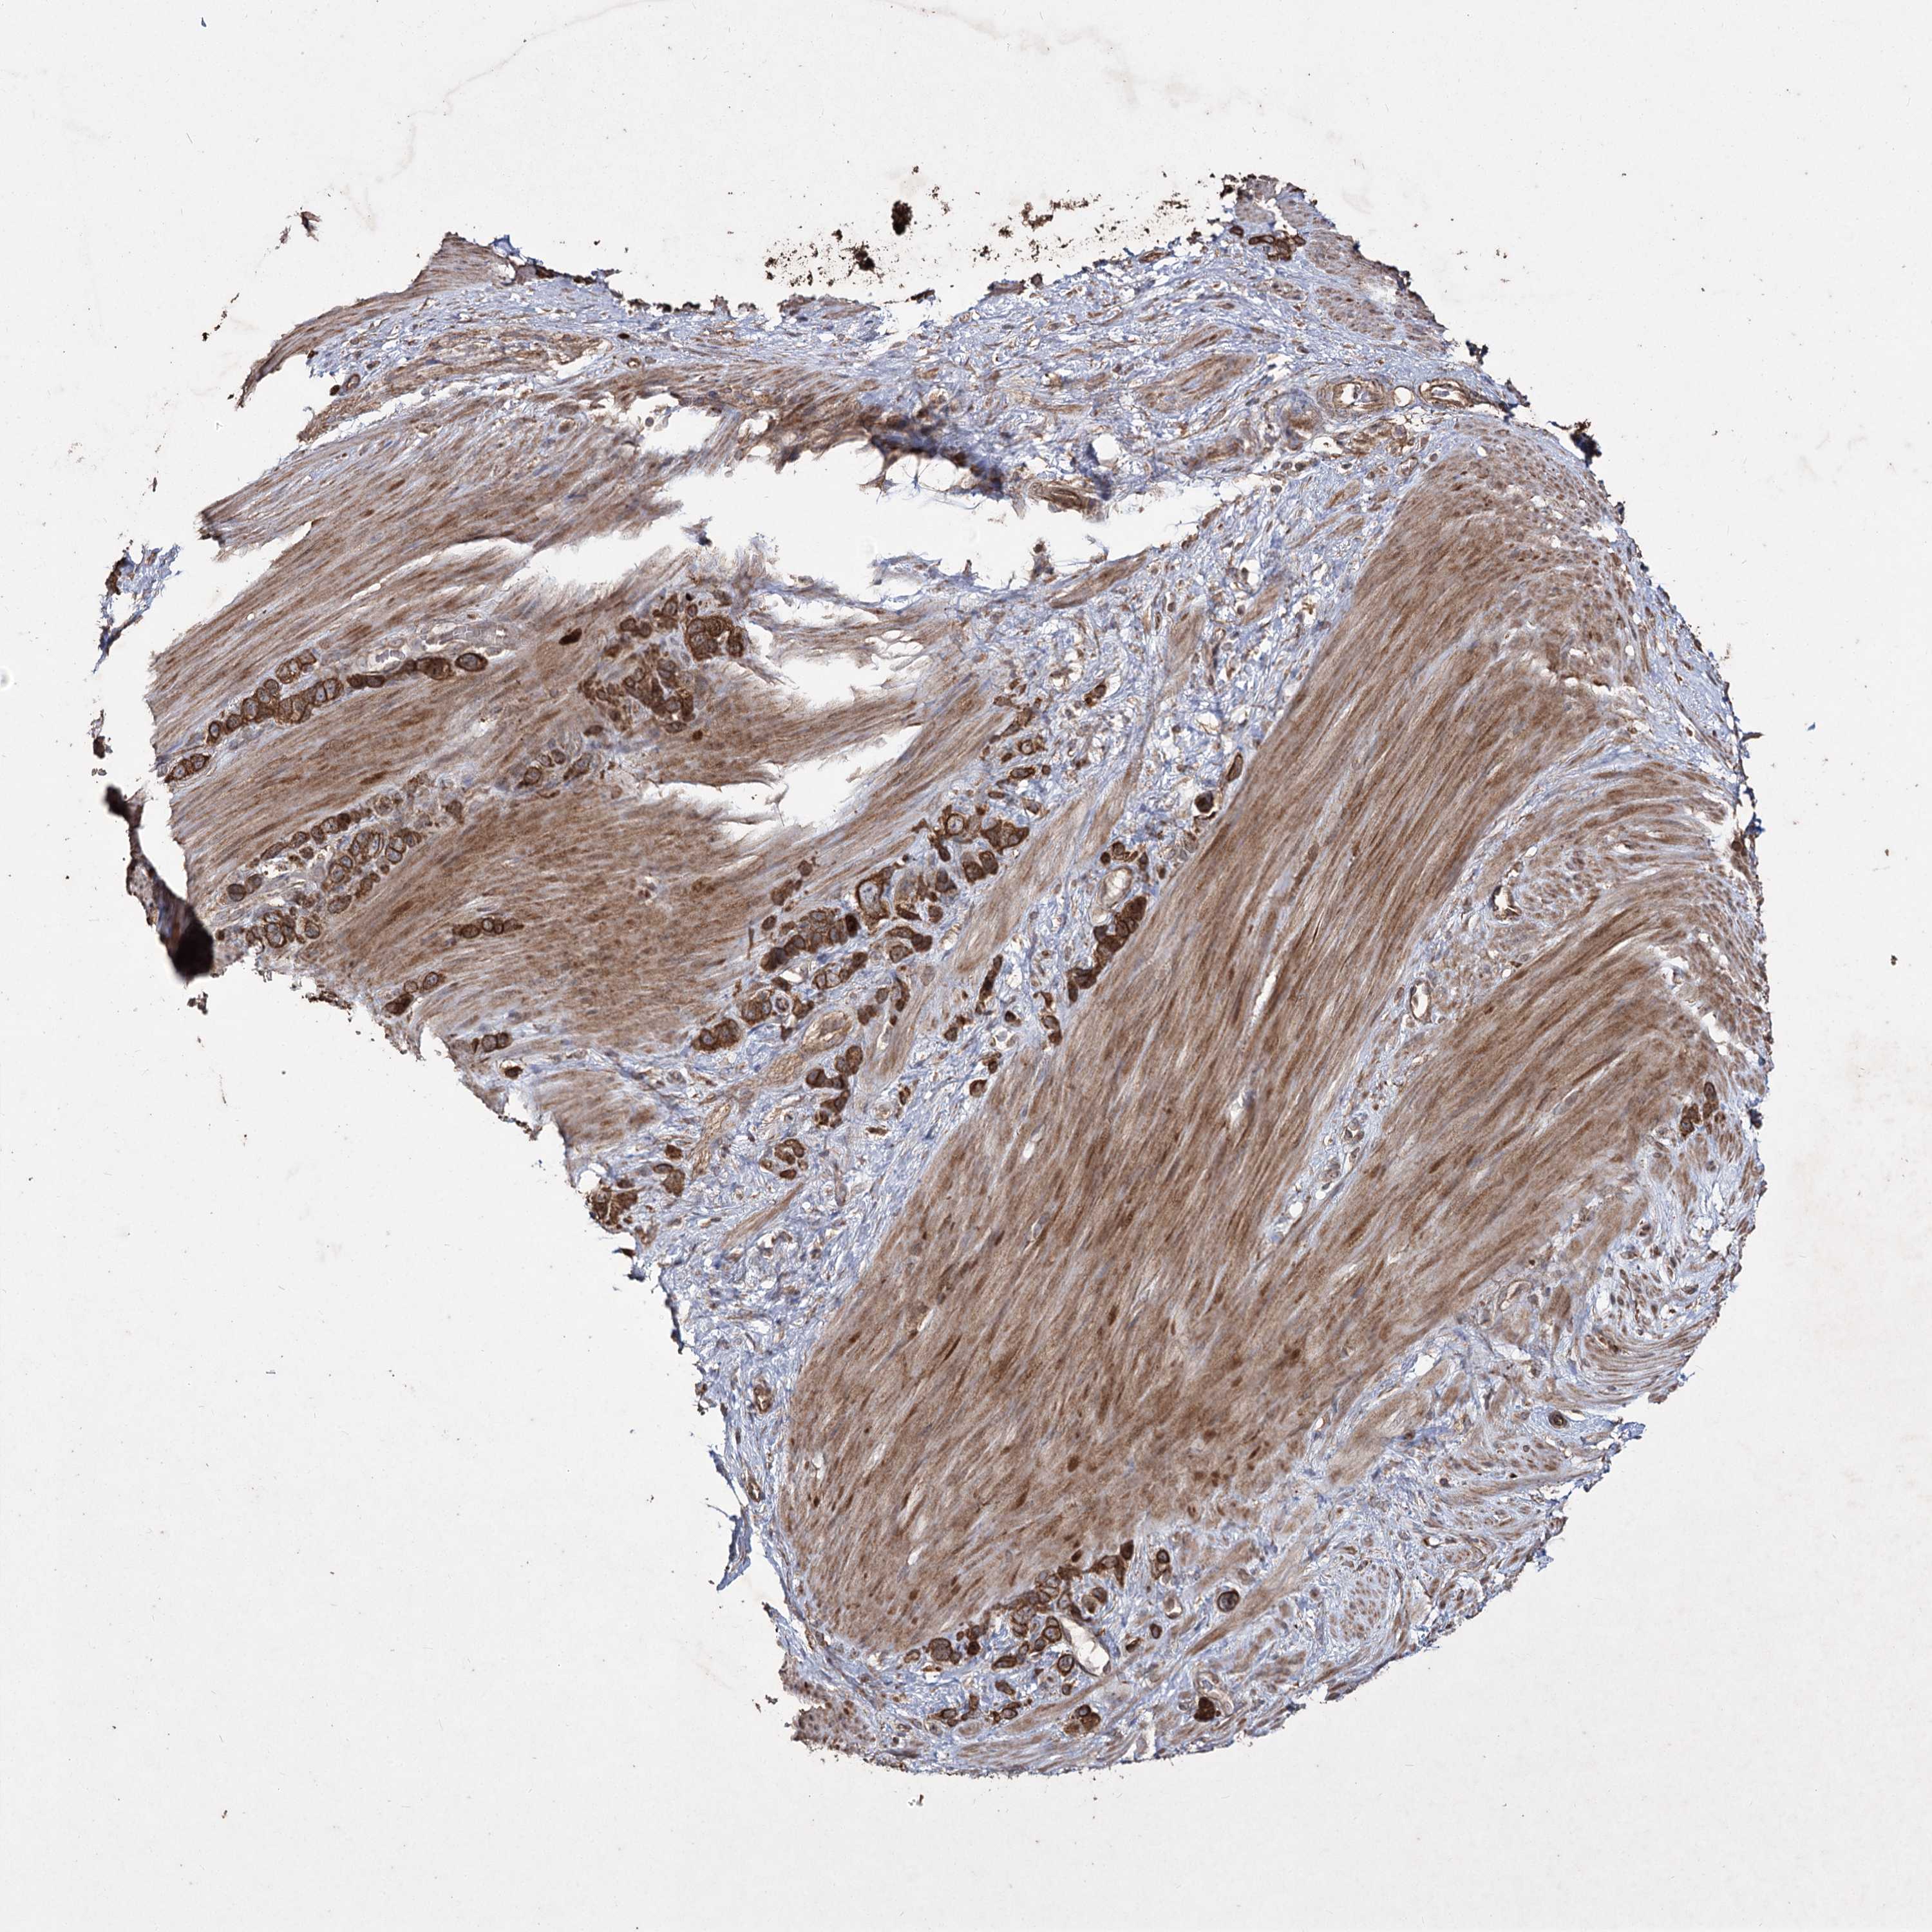

STOMACH CANCER - Protein expressioni

A mouse-over function shows sample information and annotation data. Click on an image to view it in a full screen mode. Samples can be filtered based on level of antibody staining by selecting one or several of the following categories: high, medium, low and not detected. The assay and annotation is described here.

Antibody stainingi

Antibody staining in the annotated cell types in the current human tissue is reported as not detected, low, medium, or high, based on conventional immunohistochemistry profiling in selected tissues. This score is based on the combination of the staining intensity and fraction of stained cells.

Each image is clickable and will lead to virtual microscopy that enables deeper exploration of all samples and also displays staining intensity scores, fraction scores and subcellular localization as well as patient and tissue information for each sample.

Staining

High

Medium

Low

Not detected

Intensity

Strong

Moderate

Weak

Negative

Quantity

>75%

75%-25%

<25%

None

Location

Nuclear

Cytoplasmic/membranous

Cytoplasmic/membranous,nuclear

Adenocarcinoma, NOS